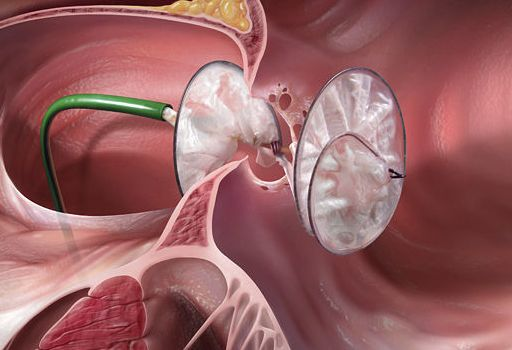

房间隔缺损 (Atrial Septal Defect ,ASD)是指分隔右心房和左心房的壁上的出现破损。ASD会增加流经肺部的血液量,随着时间的推移,会损坏肺部血管。

室间隔缺损 (Ventricle Septal Defect ,VSD)是指分隔右心室和左心室出现破损。VSD使得血液可以从左心室渗入右心室,造成更多的血液被泵入肺部,迫使心脏和肺部更加努力地工作。

先天性心脏病的经导管封堵;